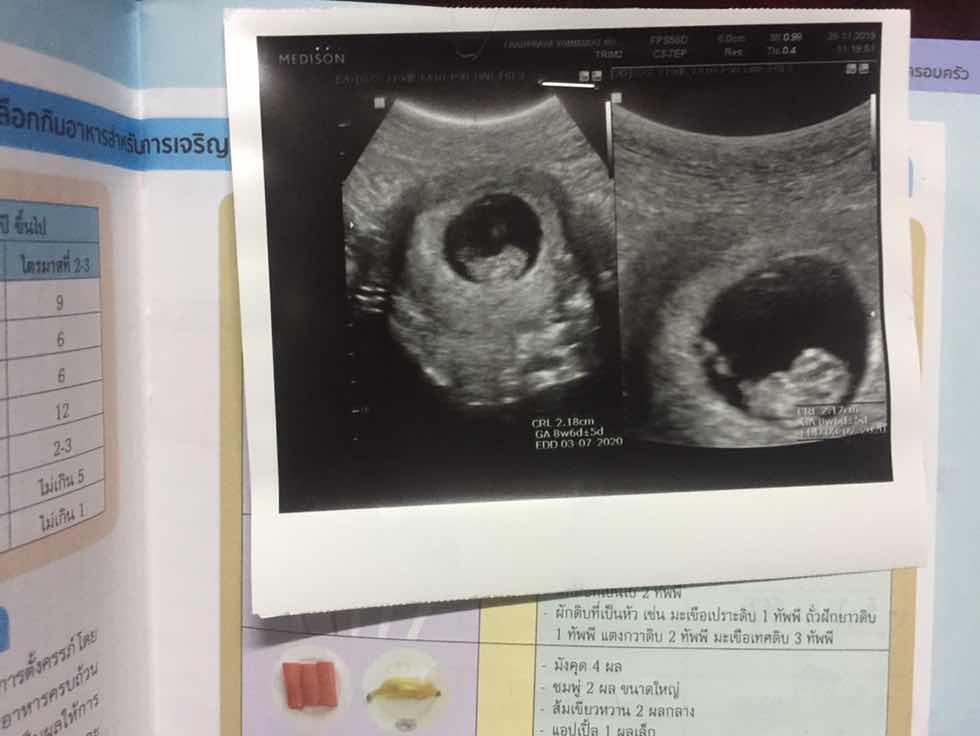

ตอนนี้อายุครรภ์6สัปดา แต่ยังไม่เห็นตัวน้องคะ เห็นแต่ถุง แอบกังวลนิดๆ

ซาวด์ทางหน้าท้องหรือช่องคลอดคะแม่ ถ้าทางหน้าท้อง ถ้าตัวอ่อนยังเล็กมากๆ หรือเป็นคนหน้าท้องหนา อาจจะยังไม่เห็นค่ะแม่ ทางช่องคลอดจะพอมีลุ้นมากกว่าค่ะ ทั้งนี้เป็นไปได้ว่า อายุครรภ์อาจจะน้อยกว่าที่นับ เพราะไข่อาจจะตกช้ากว่ากำหนด ตัวอ่อนยังเล็กมากอยู่ จึงยังไม่พบ ก็เป็นได้ค่ะแม่ ทานโฟลิคทุกวัน พักผ่อนเยอะๆ นะคะ ซาวด์ครั้งหน้าอาจจะได้เจอกันแล้วจ้า